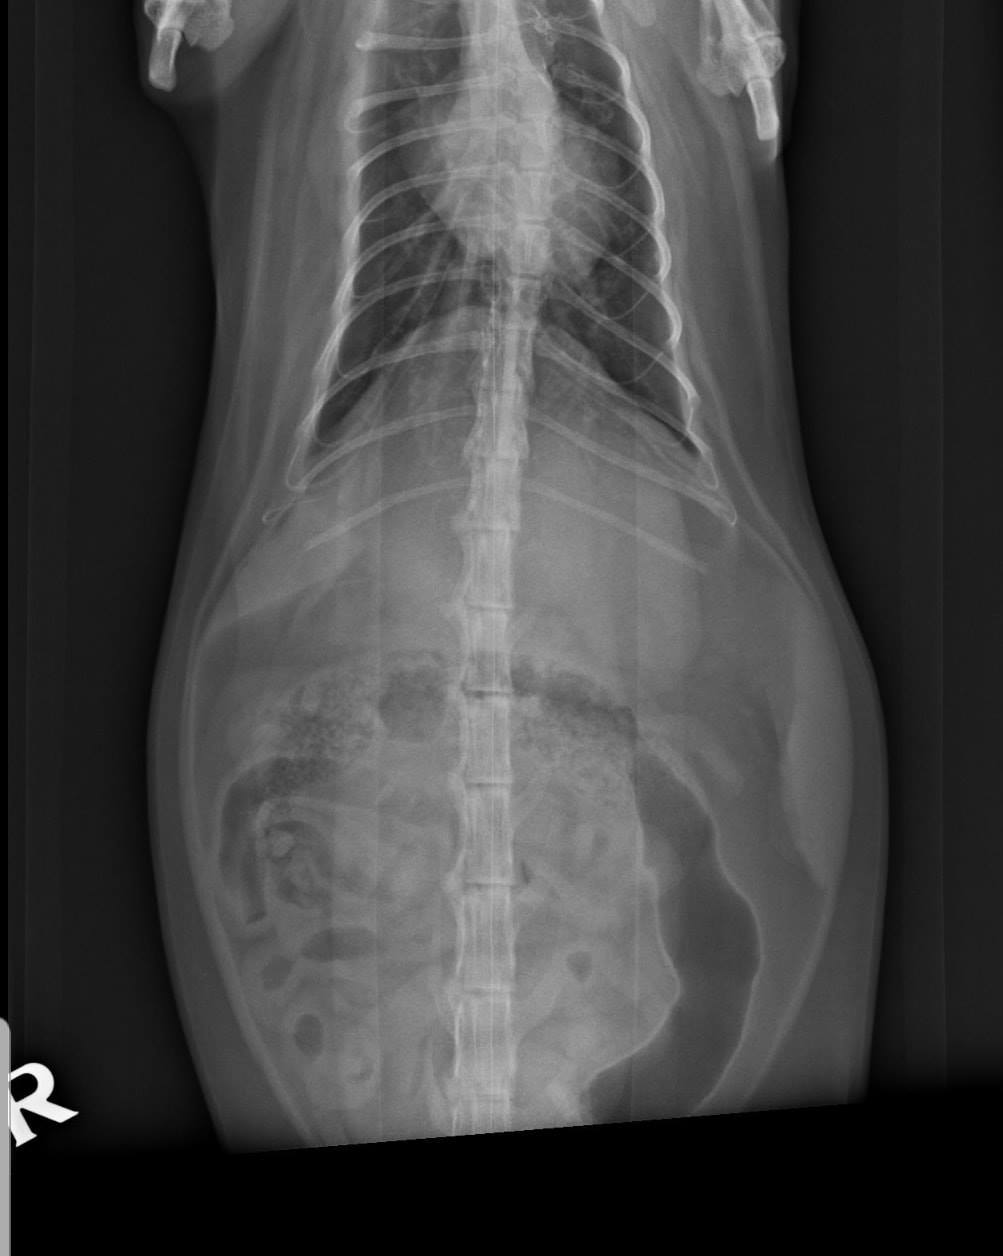

Po sérii vyšetření a RTG byla Donikovi nasazena chemoterapie! 😯

Drobné útvary nádoroveho bujení po celých plicích potvrdila i biopsie.